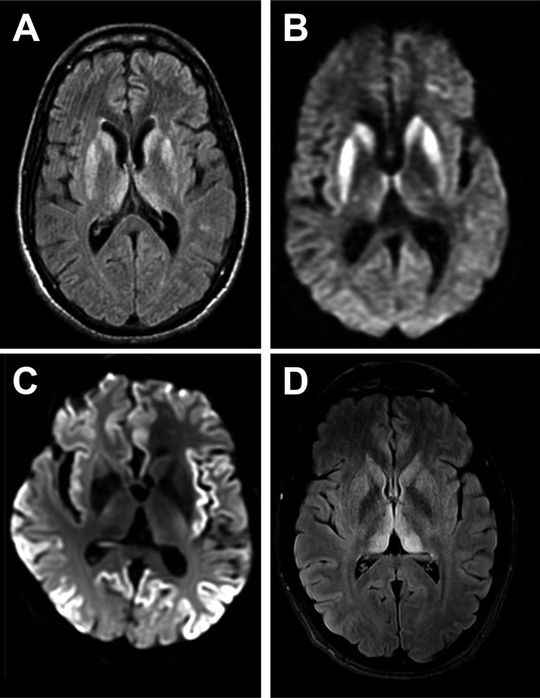

65 year old male with ataxia and cognitive disorder

CTJ disease

CJD disease